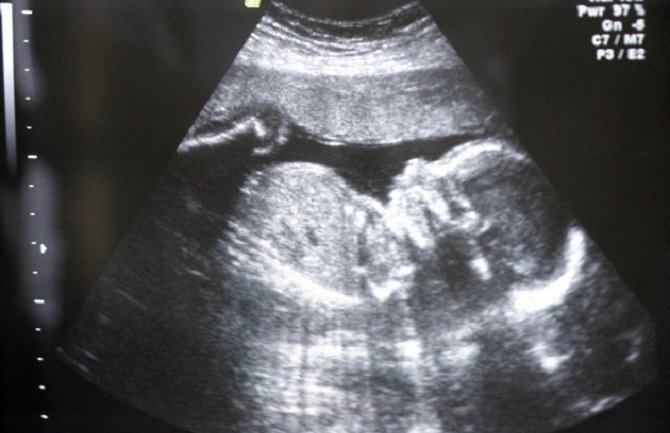

Kao i većina drugih zemalja Evrope, sadašnji španski zakon dozvoljava abortus u prvih 14 nedjelja trudnoće, a novopredloženi zakon omogućava prekid trudnoće jedino u slučajevima silovanja ili ukoliko je drugo stanje žene opasnost za njeno zdravlje, što mora biti dokazano medicinskom dokumentacijom, prenijela je agenciaj Rojters.